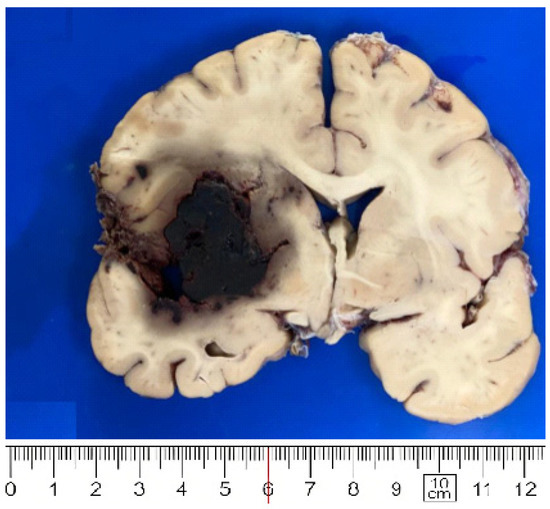

| Infarction | 3 (27%) | 1 (11%) | 1 (7%) |

| Parenchymal hemorrhage | 0 (0%) | 0 (0%) | 1 (7%) |

| Herniation | 2 (18%) | 1 (11%) | 1 (7%) |